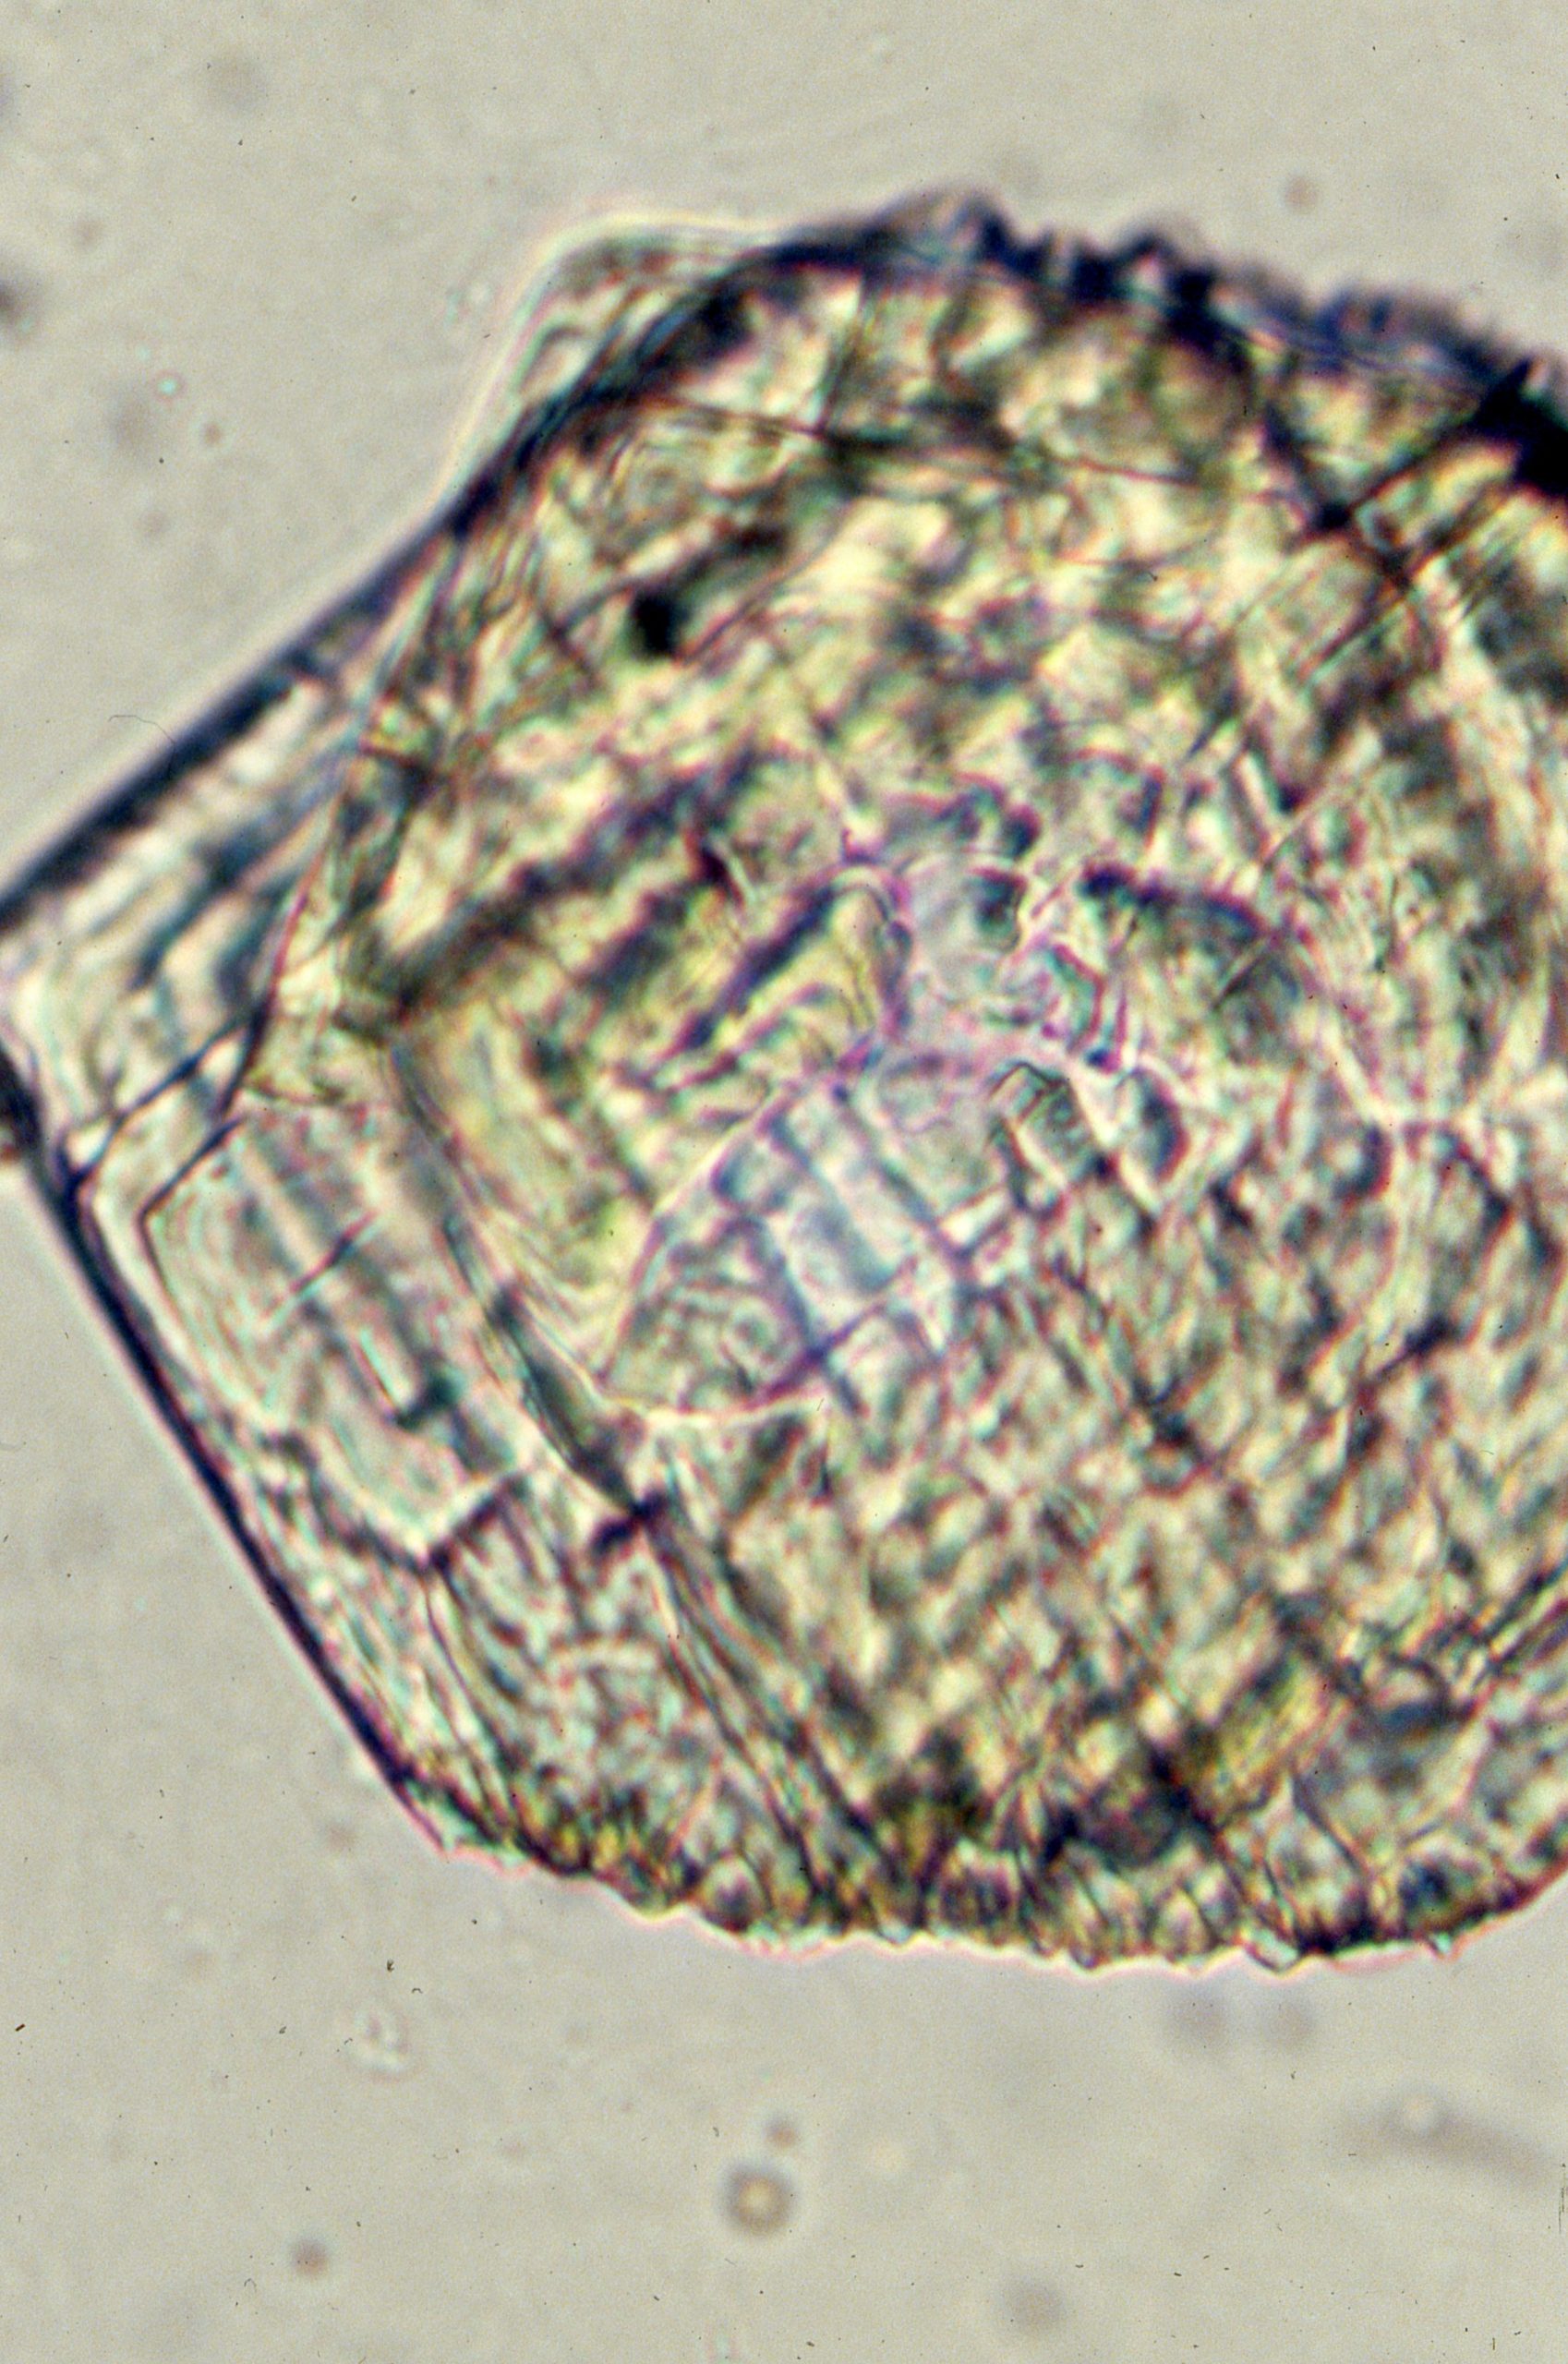

Uric acid crystals are found in acid urine, the crystal vary more in morphology than any other type of crystalThe morpholoy varies from needles, hexagonal, whestone forms, rosttes or rhombic plates Mag 10X Mag 10X Mag 10xX Mag 40X Mag 40X Mag 40X Mag 40x Mag 40X The above microphotographs are uric acid crystal with polarized light